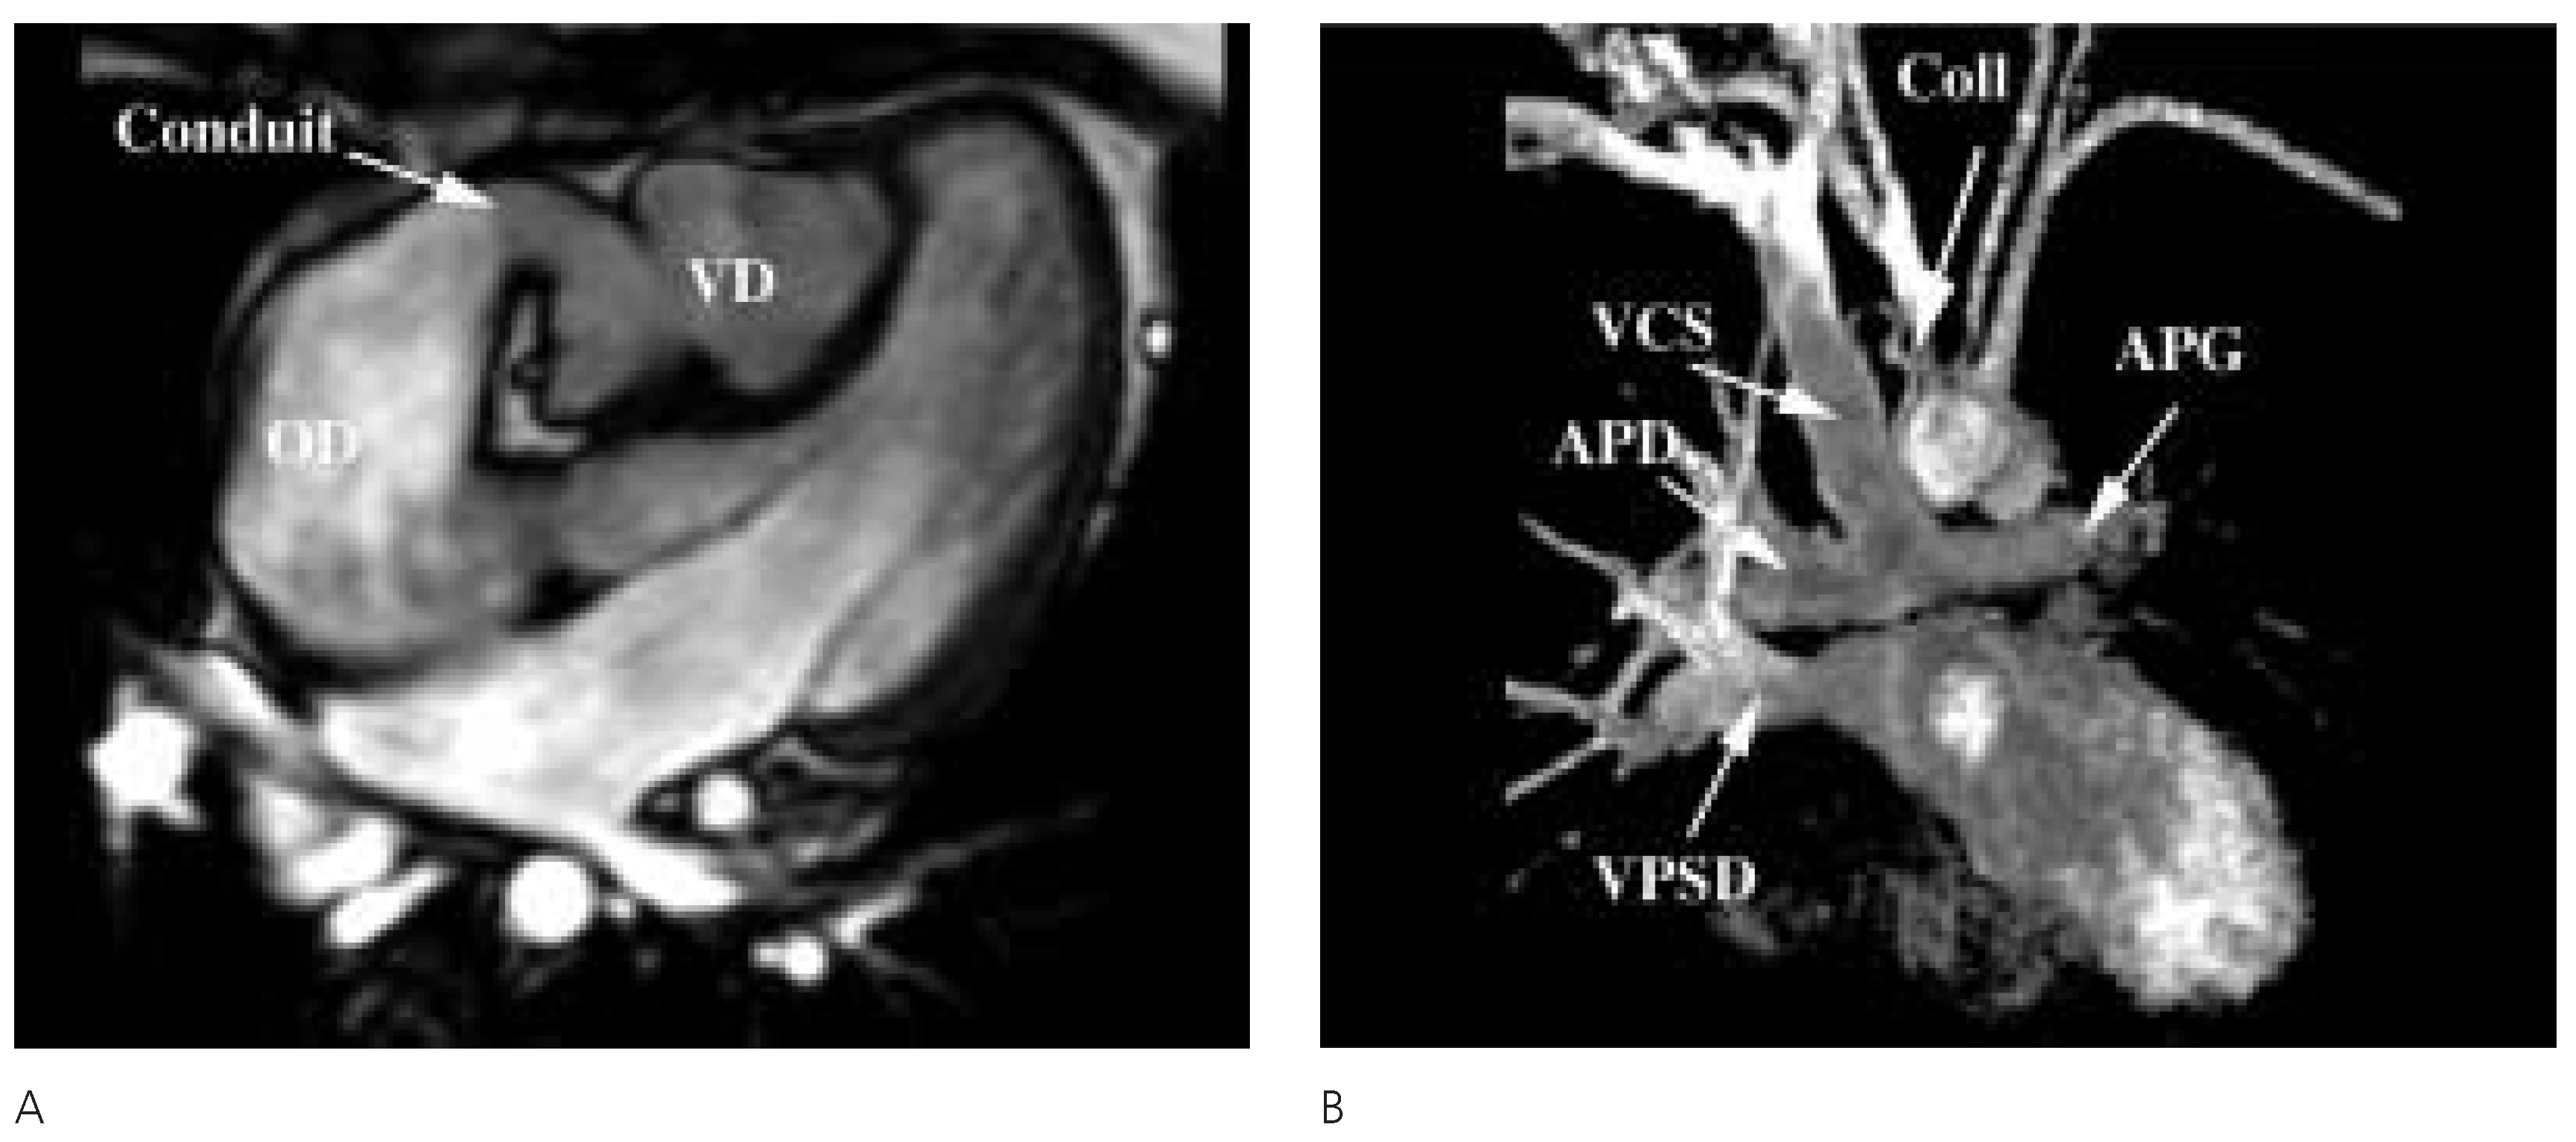

Description du cas